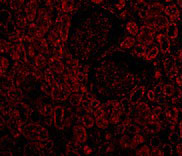

Immunofluorescence of Bcl-2 in Human Kidney cells with Bcl-2 antibody at 10 μg/mL. |